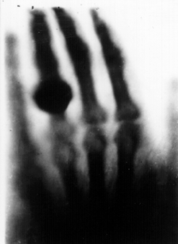

DNA first identified

James Watson and Francis Crick demonstrate a structural model for deoxyribonucleic acid (DNA) as a double helix twisted ladder. Which is essential to understanding how genes control the chemical processes in living organisms.

They are assisted when Maurice Wilkins shows James an X-ray crystallography image of DNA made by Rosalind Franklin. Watson recognizes a double helix, he and Francis Crick publish it, and win a Nobel Prize for it in 1962.

Dorothy Crowfoot Hodgkin spends years perfecting the X-ray crystallography technique, for which she wins a Nobel Prize in 1964. She also determines the structures of penicillin, vitamin B12 and insulin.